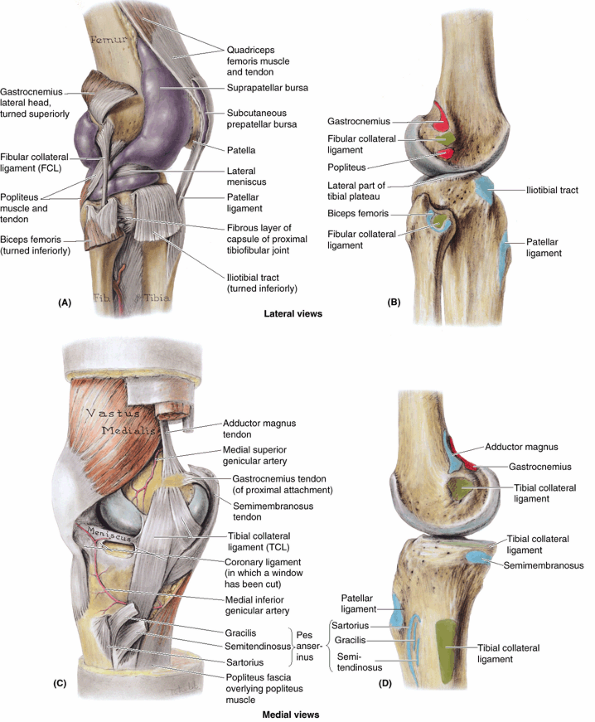

and knee extension are used during the swing phase of level walking and

so are not weight-bearing actions; however, they are effected by body

weight when their eccentric contraction is necessary for deceleration

or walking downhill or down stairs

locomotion. The invertors and evertors of the foot are principal

stabilizers of the foot during the stance phase. Their long tendons,

plus those of the flexors of the digits, also help support the arches

of the foot during the stance phase, assisting the intrinsic muscles of

the sole.

calcaneal tendon is ruptured, a much less effective and efficient push

off (from the midfoot) can still be accomplished by the actions of the

gluteus maximus and hamstrings in extending the thigh at the hip joint

and the quadriceps in extending the knee. Because push off from the

forefoot is not possible (in fact, the ankle will be passively

dorsiflexed as the body’s weight moves anterior to the foot), those

attempting to walk in the absence of plantarflexion often rotate the

foot as far laterally (externally) as possible during the stance phase

to disable passive dorsiflexion and allow a more effective push off

through hip and knee extension exerted at the midfoot.

region is closely associated with the assumption of bipedalism and an

erect posture. The prominent gluteal region is unique to humans.

Modification of the shape of the femur necessary for bipedal walking

and running (specifically the “bending” of the bone, creating the angle

of inclination and the trochanters, as discussed earlier in this

chapter) allows the superior placement of the abductors of the thigh

into the gluteal region. The remaining thigh muscles are organized into

three compartments by intermuscular septa that pass deeply between the

muscle groups from the inner surface of the fascia lata to the linea

aspera of the femur (Fig. 5.10D). The

compartments are anterior or extensor, medial or adductor, and posterior or flexor,

so named on the basis of their location or action at the knee joint.

Generally, the anterior group is innervated by the femoral nerve, the

medial group by the obturator nerve, and the posterior group by the

tibial portion of the sciatic nerve. Although the compartments vary in

absolute and relative size depending on level, the anterior compartment

is largest overall and includes the femur.

|

Table 5.2. Muscle Action during the Gait Cycle

|||||||||||||||||||||||||||||||||||||||||||||||||||||||||||||||||||||||||||||||||||||||||||||||||||||

|---|---|---|---|---|---|---|---|---|---|---|---|---|---|---|---|---|---|---|---|---|---|---|---|---|---|---|---|---|---|---|---|---|---|---|---|---|---|---|---|---|---|---|---|---|---|---|---|---|---|---|---|---|---|---|---|---|---|---|---|---|---|---|---|---|---|---|---|---|---|---|---|---|---|---|---|---|---|---|---|---|---|---|---|---|---|---|---|---|---|---|---|---|---|---|---|---|---|---|---|---|---|

used in dissection courses, the anterior and medial thigh is addressed

initially, followed by continuous examination of the posterior aspect

of the proximal limb: gluteal region, posterior thigh, and popliteal

fossa

The major muscles of the anterior compartment tend to atrophy

(diminish) rapidly with disease, and physical therapy is often

necessary to restore strength, tone, and symmetry with the opposite

limb after immobilization of the thigh or leg.

quadrangular muscle located in the anterior part of the superomedial

aspect of the thigh. It often appears to be composed of two layers,

superficial and deep, and these are generally innervated by two

different nerves. Because of the dual nerve supply and the muscle’s

actions (the pectineus adducts and flexes the thigh and assists in

medial rotation of the thigh), it is actually a transitional muscle